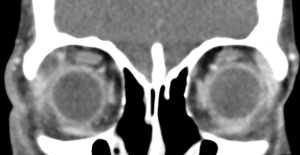

A contrast-enhanced computed tomography (CT) scan of the orbits will show enlargement of the lacrimal gland with a hypodensity and peripheral enhancement consistent with an abscess.[13][14] There may also be loculations of the abscess and fat stranding of the surrounding periorbita. On Magnetic Resonance Imaging (MRI) with diffusion-weighted imaging there may be restricted diffusion within the abscess.[14]